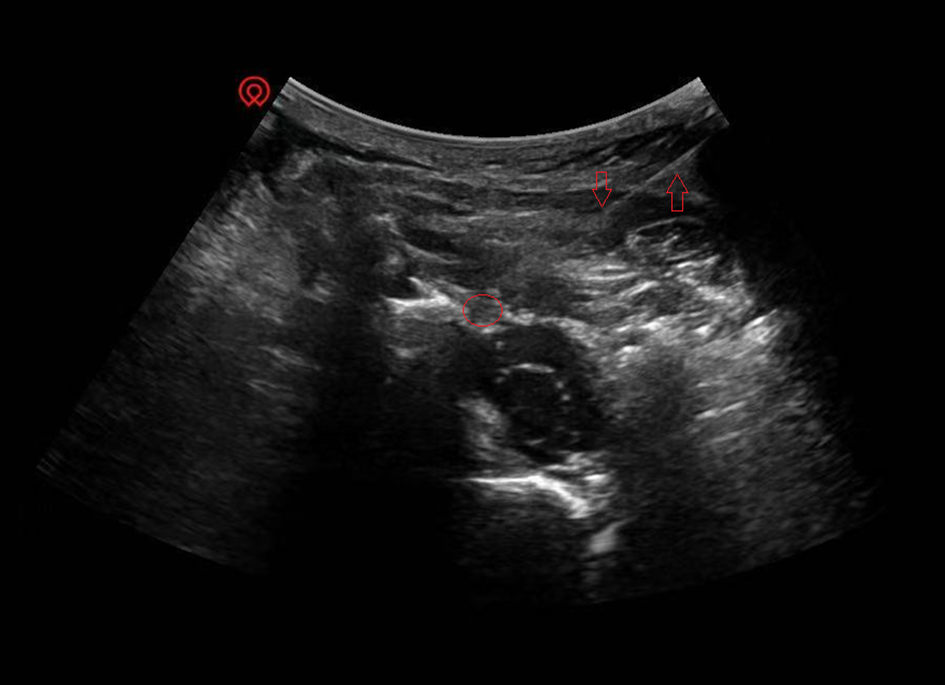

对顽固性颈源性头痛患者,潍坊市中医院疼痛科开展了介入治疗,超声引导下颈2背根节射频消融术。

圆圈为颈2背根神经节,箭头为穿刺射频针

颈2背根神经节是上传后枕部感觉的“第一站中转站”,也是与三叉神经发生“信号混淆”的关键节点。当颈部结构长期劳损、炎症刺激或受到卡压时,这个“中转站”会变得异常兴奋,持续向大脑发送错误的疼痛信号。因此,调节它的兴奋性,就成为治疗的核心。